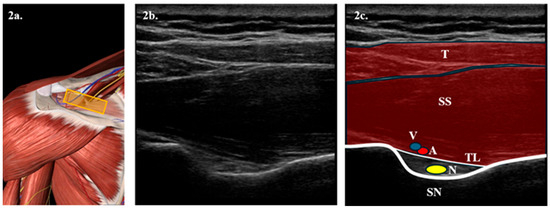

- Secondly, after 15 min of the SSNB, ultrasound-guided HD will begin. To perform this, the patient will be placed in a lateral decubitus position on the healthy arm. The arm to be treated will be positioned at the patient’s side without forcing its extension. The joint cavity will then be approached posteriorly, introducing a spinal needle in the ultrasound plane between the humeral cortex and the labrum. The joint cavity will then be confirmed by introducing physiological saline solution and verifying its reflux by pushing the plunger. Subsequently, 5 mL of 0.25% bupivacaine + 0.5 mL of triamcinolone acetonide will be introduced, topping up the predetermined volume with saline solution later. Figure 3.

Figure 3. Illustration of access point for posterior approach HD technique. (a) Anatomical representation of the posterior articular recess seen from behind, obtained from Essential Anatomy 5 after removing the plane of the deltoid muscle. The yellow rectangle represents the position of the probe. (b) Longitudinal ultrasound section with a 6–15 MHz linear probe of the posterior articular recess. (c) Representation of the most notable anatomical structures in the posterior articular recess. In the foreground, we see the deltoid muscle (D) and below it, the infraspinatus muscle (IS). Two hyperechoic lines are observed, corresponding to the cortices of the glenohumeral recess (GR) and the humeral head (H). Between them, the labrum (L) appears, represented as a gray triangle. The dashed arrow represents the path of the needle toward the joint cavity, represented in blue. - -